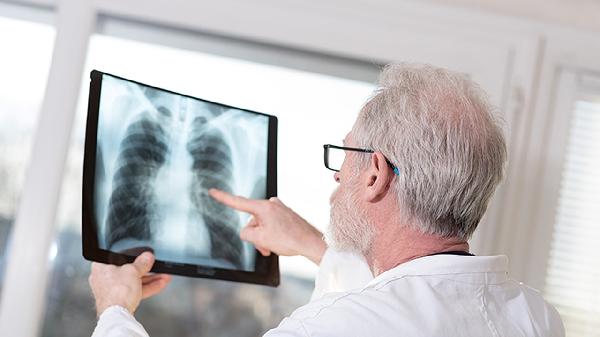

糖尿病、矽肺、慢性腎功能不全等疾病患者更易繼發(fā)肺結(jié)核。血糖控制不佳的糖尿病患者結(jié)核發(fā)病率顯著增高。這類患者需積極治療原發(fā)病,定期進(jìn)行胸部X線檢查。治療時需注意抗結(jié)核藥物與基礎(chǔ)疾病用藥的相互作用,如利福平膠囊可能減弱降糖藥效果。